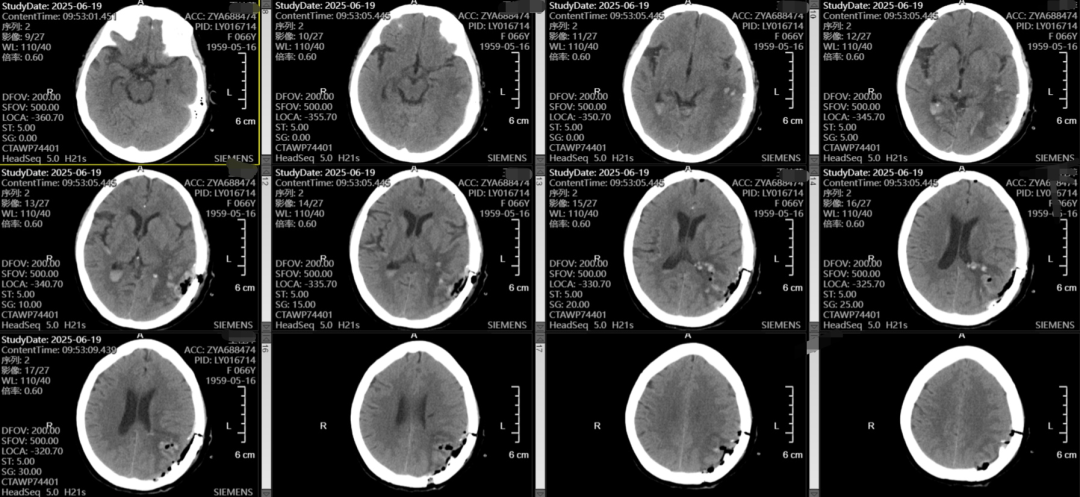

随着老龄化的加剧,脑出血的患者越来越多,不同部位的脑出血,可能因不同的原因导致,该患者左侧颞枕叶脑出血,吴全主任考虑脑血管畸形可能较高,但患者意识渐昏迷,先行血肿清除,但骨窗主要位于后枕顶部,若是去除骨瓣,不利于术后脑组织的保护,且后期需要颅骨修补,故与患者家属充分沟通后,予以骨瓣回纳,术后治疗上加强脱水,帮助患者渡过脑水肿关,患者术后第一天意识即转清楚。后期待病情平稳后在行DSA检查评估,明确此次出血是否为脑血管畸形、动脉瘤等原因导致的出血。